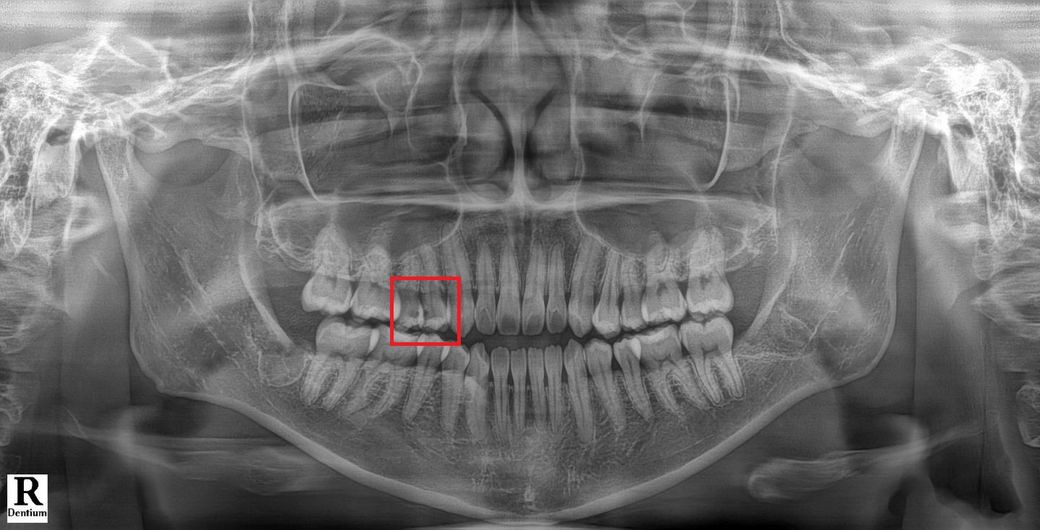

사랑니 발치후 다른 치아 인접면 충치치료 가능 시기는 언제인가요?

오른쪽 송곳니 옆에 인접면 충치가 있더라구요.

• 1번 째 사진

사랑니 뽑은 후 1주일 후에 실밥 푸니, 1주일 이후에는 치료하면 됩니다. x ray 사진상에서 충치 많이 진행되지 않은 것으로 보이니 신경치료까지는 안해도 될 것으로 보입니다.

사진상으로 보면 충치가 꽤 깊어 보입니다. 신경치료 가능성이 있어 보입니다. 사랑니 발치후 1-2주 정도 지나시면 치료를 받으셔도 됩니다.

일주일 후에 실밥을 푸신 후에 바로 치료를 하실 수 있습니다. 신경치료 여부는 충치의 범위에 따라 다르며 충치를 제거해봐야 알 수 있습니다.